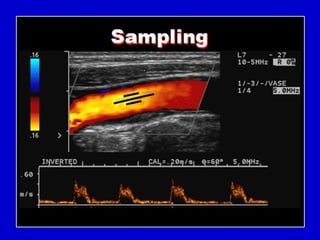

Doppler Sampling

Spectral Doppler